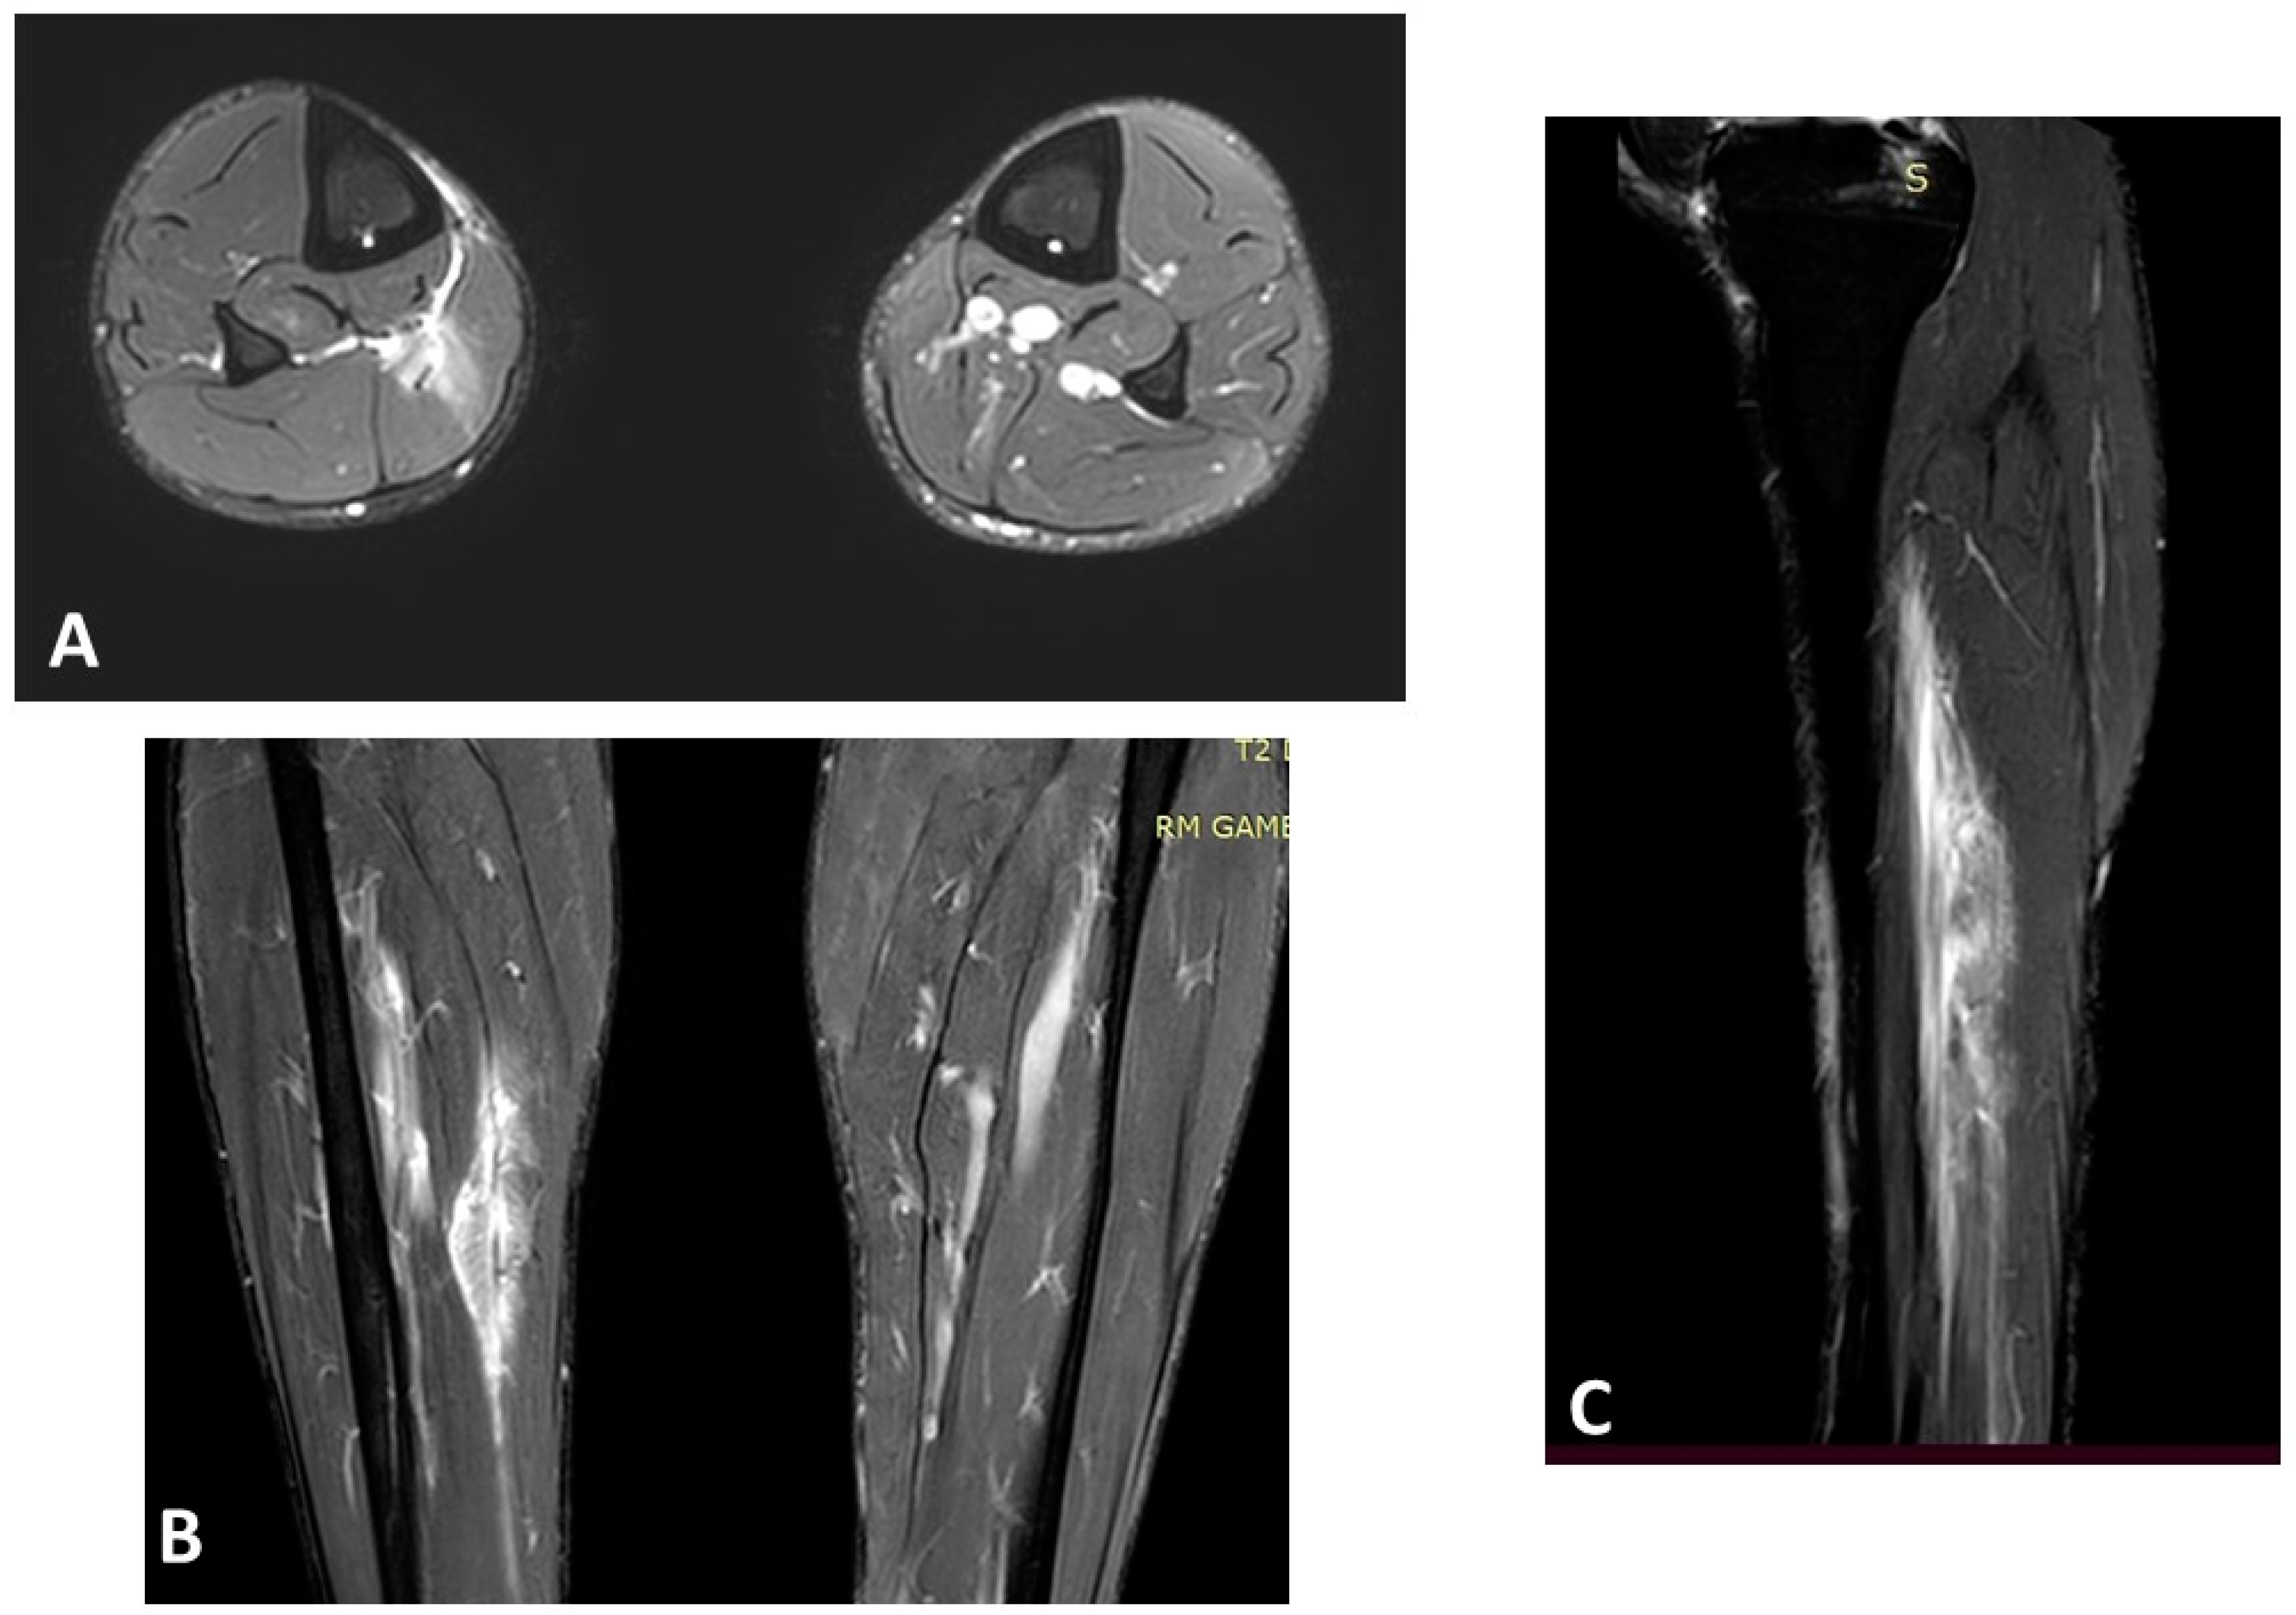

- Balius, R.; Alomar, X.; Rodas, G.; Miguel-Pérez, M.; Pedret, C.; Dobado, M.C.; Blasi, J.; Koulouris, G. The Soleus Muscle: MRI, Anatomic and Histologic Findings in Cadavers with Clinical Correlation of Strain Injury Distribution. Skeletal Radiol. 2013, 42, 521–530. [Google Scholar] [CrossRef] [PubMed]

- Isern-Kebschull, J.; Pedret, C.; Mechó, S.; Pruna, R.; Alomar, X.; Yanguas, X.; Valle, X.; Kassarjian, A.; Martínez, J.; Tomas, X.; et al. MRI Findings Prior to Return to Play as Predictors of Reinjury in Professional Athletes: A Novel Decision-Making Tool. Insights Imaging 2022, 13, 203. [Google Scholar] [CrossRef] [PubMed]